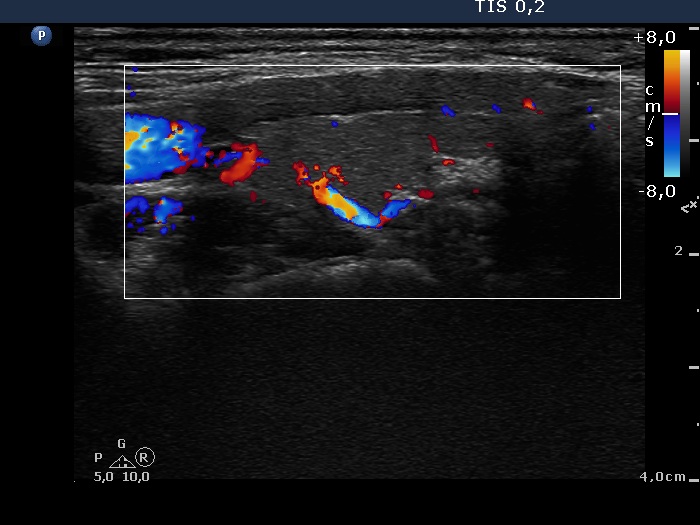

Discrete lesion or nodule in Hashimoto's thyroiditis - case 26 (1048) (ultrasonographic picture 7)

Left lobe, longitudinal scan, color Doppler mode. The vascularization is not specific.